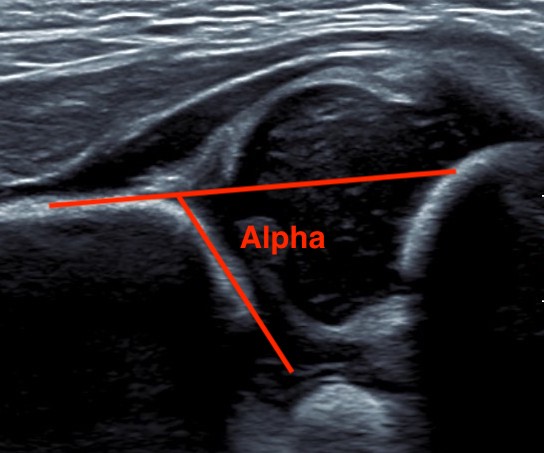

| Alpha Angle | Beta Angle | Dynamic |

|---|---|---|

|

Between ilium & bony roof acetabulum

Normal > 60°

The lower the alpha angle, the more subluxed the hip is

Alpha angle between ilium and bony roof of acetabulum